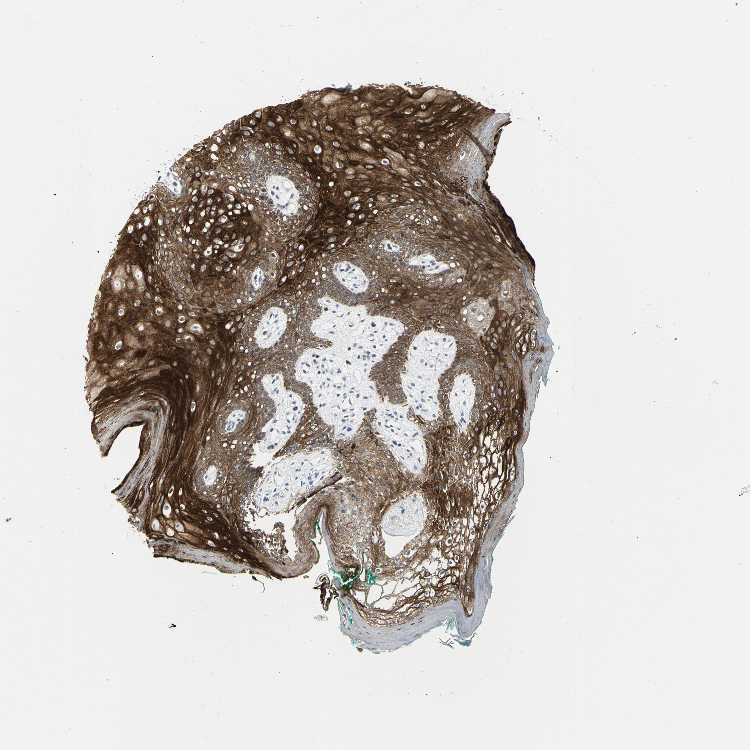

TISSUE PRIMARY DATA ORAL MUCOSA Show tissue menu

ORAL MUCOSA - Antibody stainingi

Antibody staining in the annotated cell types in the current human tissue is reported as not detected, low, medium, or high, based on conventional immunohistochemistry profiling in selected tissues. This score is based on the combination of the staining intensity and fraction of stained cells.

Each image is clickable and will lead to virtual microscopy that enables deeper exploration of all samples and also displays staining intensity scores, fraction scores and subcellular localization as well as patient and tissue information for each sample.

Antibody HPA006914Antibody CAB004563

Squamous epithelial cells MediumHigh